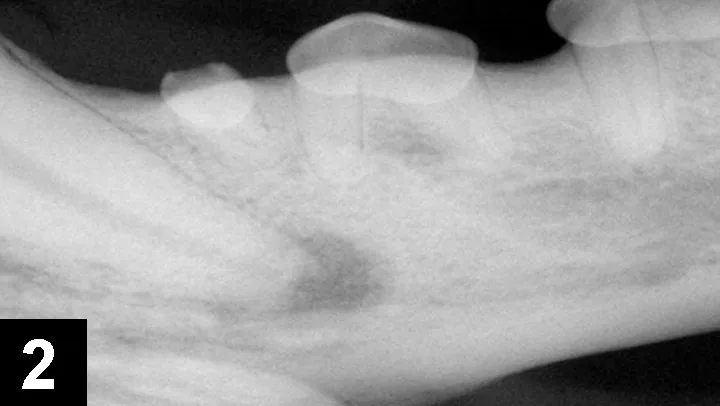

4. Maxillary draining tracts

A maxillary extraoral draining tract rostral to the eye is most commonly associated with chronic infection (periodontal or endodontic) of a maxillary premolar or molar tooth (Figure 6). In brachycephalic breeds, it might even be the canine tooth. Dental disease is subgingival, and both periodontal and endodontic infections can result in maxillary draining tracts. There may be associated bone proliferation or reaction, and the region may be firm on palpation. Dental disease should be the top differential for these lesions before dermatologic conditions, ophthalmologic conditions, or tumors are considered. The infected tooth can be identified with general anesthesia, oral examination, periodontal probing, and intraoral radiographs of the maxillary regional dentition on the ipsilateral side of the draining tract (Figures 7 and 8) with similar radiographs of the contralateral side for comparison. Surgical extraction of the infected tooth or teeth is often necessary. The carnassial tooth is not always at fault; therefore, intraoral radiographs are needed to diagnose the infected tooth, which could be any of the ipsilateral dentition (eg, first maxillary molar).